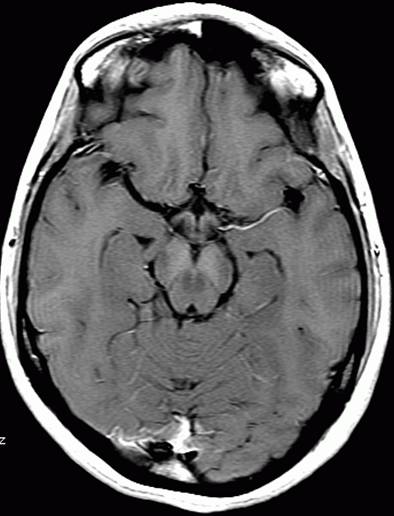

FLARI序列就是通俗所说的压水像,在这个序列中,脑灰质是高信号,也就是亮一些的,脑白质是低信号--这些类似于T2WI序列--但是在压水像上,脑脊液的信号是低的,也就是黑色的。这也是之所以称之为压水像的原因。

FLAIR 水抑制成像对脑部病理改变具有高度的敏感性,减轻水信号干扰,显示病理改变,鉴别病灶处是否为自由水,自由水为低信号。TR:9000ms TE:120ms TI:2500ms DWI:弥散加权成像,是目前能够检测活体组织内水分子扩散运动的无创性方法,是诊断脑梗塞最敏感的序列,超急性脑梗塞(小于6小时)细胞毒性水肿可明确诊断。TR:1500---2500ms TE:15---30ms

FLARI序列就是通俗所说的压水像,在这个序列中,脑灰质是高信号,也就是亮一些的,脑白质是低信号--这些类似于T2WI序列--但是在压水像上,脑脊液的信号是低的,也就是黑色的。这也是之所以称之为压水像的原因。 STIR脂肪抑制序列,在通常的T1WI和T2WI像上,脂肪都是高信号--亮的,在脂肪抑制序列--有许多种,频率抑制啊翻转恢复啊,正反相位啊--你不用明白这么许多,只要知道是压脂的序列,那么这个图像上的脂肪就是低信号--黑的。比如平时的腹部皮下脂肪,头皮下脂肪,就变成了黑色的。 一般的图像上,都会标出来FS--既是压脂序列。 DWI就是平时头部磁共振影像看起来分辨率非常差,颗粒很粗的序列,现在在临床上主要用于急性脑缺血的早期诊断,早期,脑哽塞病灶,在这个序列上是高信号的--是由于细胞毒性水肿造成扩散降低造成的。 DWI空间分辨率相对较低,靠近脑底处的磁敏感性伪影对额叶底部,颞极,小脑等处的病变评价带来影响,FLAIR不受影响。DWI上脑脊液为游离液体,其ADC类似于纯水,弥散快,在DWI上脑脊液信号明显衰减,也产生FLAIR中的黑液体效应,但二者的对比不完全相同,FLAIR除液体相为黑色外,其他组织保持T2对比。DWI的对比取决于另一组织特性参数ADC。DWI较FLAIR敏感,病变与正常组织对比更高,其异常信号范围大于常规T2和FLAIR序列。